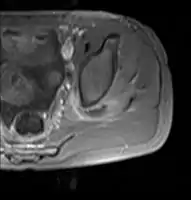

Axial T1 weighted fat suppressed post IV gadolinium contrast enhanced MRI image showing a mutliloculated bacterial abscess in the left gluteal muscle which grew Staphylococcus aureus (methicillin sensitive) thought to be due to tropical pyomyositis.

Coronal fat suppressed post contrast image showing a multiloculated bacterial abscess in the left gluteus minimus muscle due to tropical pyomyositis.